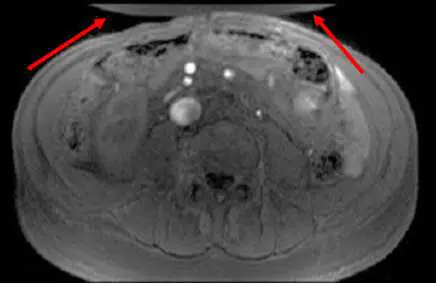

觀察本題提供的腹部橫切面(Axial)MRI影像,可以發現以下關鍵特徵:

- 空間錯置的解剖結構:在影像最上方(即患者腹壁前方,Anterior),紅色箭頭指出了兩塊呈現半月形的異常組織結構覆蓋在腹壁上。

- 摺疊現象(Wrap-around):這些多出來的組織實際上是患者位於掃描視野(Field of View, FOV)之外的解剖構造(如背部皮下脂肪、兩側手臂或側腹部組織)。因為空間編碼發生錯誤,導致 FOV 外的信號被「摺疊」或「捲褶」並疊加到影像對側(前方)。